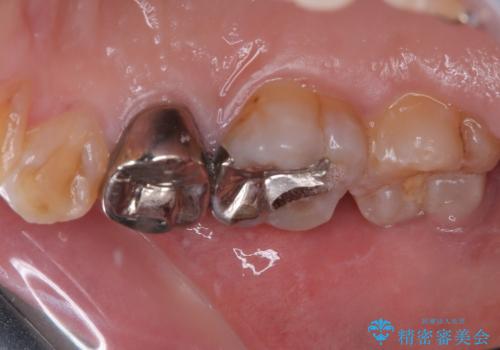

- 笑うときに目立つ銀歯を白くしたいとのことで来院された患者様です。

奥歯ではありますが、以前抜歯矯正をされているので前の方へ移動しており、非常に目立っていました。